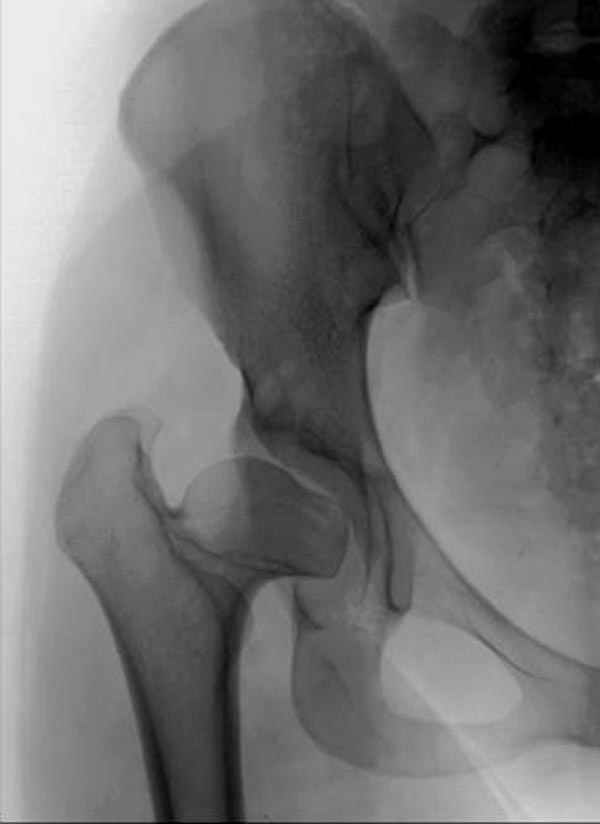

It appears that this patient has bilateral congenital hip displasia, as presented on the radiographs. As shown, the problem involves both sides of the hip joint: the acetabulum and proximal femur.

This patient is noted to have a very vertical joint surface orientation, as well, with retroversion of the acetabulum.

In this patient, it appears that addressing either the femur or the acetabulum will be insufficient to help correct this patient’s problem. It would be necessary to approach both sides of the hip joint to correct the hip dysplasia.

Pic. 1-5 preop plan; 6-8 similar case